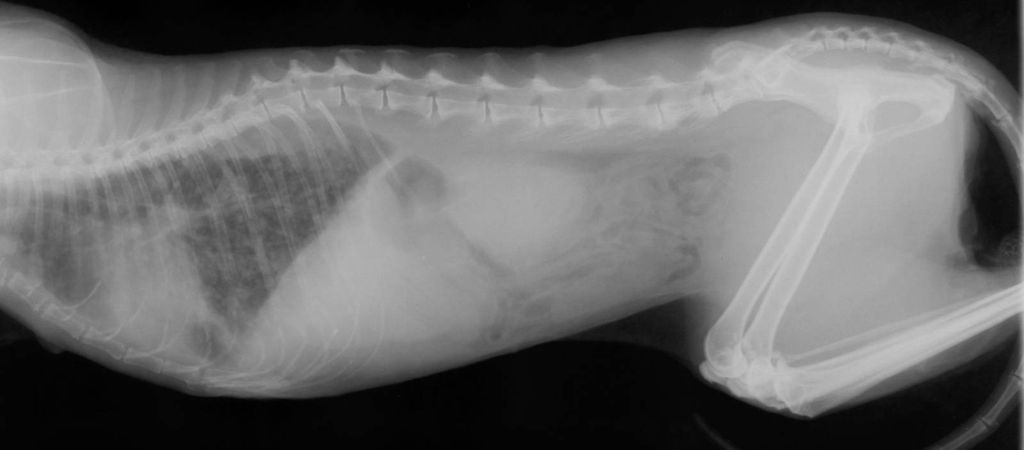

Рентгенография грудной клетки (РГК) — это фундаментальный и незаменимый метод диагностики в ветеринарии, который позволяет получить изображение легких, сердца, крупных сосудов и костного каркаса грудной клетки. У кошек этот метод имеет особое значение, так как многие критические заболевания, такие как отек легких, плевральный выпот или кошачья астма, проявляются одышкой и требуют немедленного принятия решений.

Кошку необходимо уложить на рентгеновский стол. Для получения качественного и информативного снимка жизненно важно выполнить две вещи: правильно уложить животное и сделать снимок на фазе максимального вдоха. Врач сделает как минимум две проекции — боковую (латеральную) и прямую (вентро-дорсальную или дорсо-вентральную). Это необходимо для того, чтобы увидеть все отделы легких и избежать наложения структур (например, сердца на легкие).

По ходу исследования делается 2 снимка: в положении на боку и на спине. Рентгенографию легких следует проводить в фазе полного вдоха и раскрытия, трахеи — полного вдоха и выдоха.Ветеринар определяет положение кота в зависимости от анатомических и физиологических особенностей. Для крупных животных более целесообразно проводить исследование в косых проекциях, маленьких — в положении на животе или спине. Поток луча в таком случае проходит по прямой, что разделяет ткань легких на 2 части.

После получения цифрового снимка врач визуальной диагностики (или кардиолог/пульмонолог) проводит его детальную расшифровку. Специалист оценивает легочный рисунок (признаки отека, пневмонии, астмы), размеры и форму сердца, а также наличие жидкости или воздуха в плевральной полости. Результатом является письменный протокол рентгенографии с заключением и рекомендациями для лечащего врача.

Рентгенографическое исследование грудной клетки позволяет своевременно обнаружить отек легких, переломы и трещины ребер, грудных позвонков. Также диагностируются патологии, связанные с сердцем, органами дыхания.

Рентгеновские снимки легких позволяют врачу-ветеринару оценить состояние легочной ткани, легочных сосудов, других структур. На полученных снимках видны аномалии в легких, заболевания, воспаления, опухоли, признаки инфекций.

При выявлении любых аномалий на снимке определяется их характер, точное положение, число, размер, форма, четкость границ.

Диагноз: Умеренное усиление интерстициального рисунка, без очаговых теней или плеврального выпота. Сердце не увеличено. Картина — начальные признаки вирусного бронхита, пневмония исключена.

Что дал рентген: позволил дифференцировать вирусное поражение от бактериальной пневмонии и сердечной недостаточности.